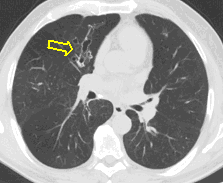

4: Miliary pattern: sarcoidosis, CT, lung window. Axial image and sagittal reformat.

A 67 year old female suffering from COPD. Bilateral rough branching interstitial widening and patchy, miliary nodules with perihilar dominance along the bronchovascular fibres and the fissures.